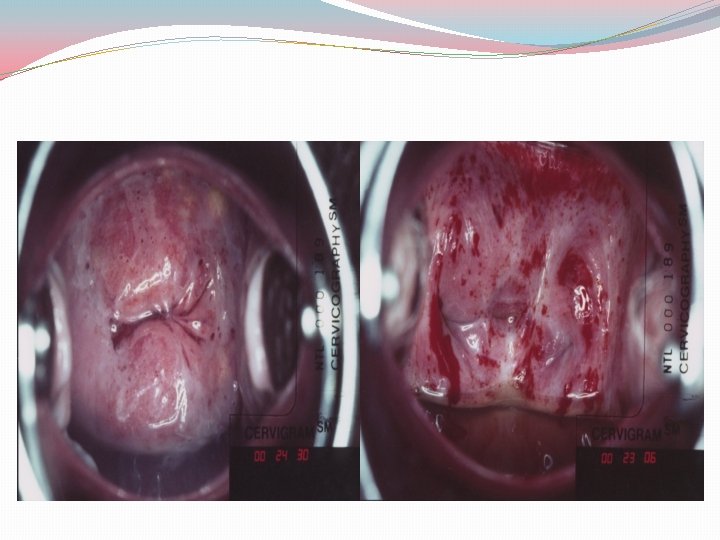

OTHER SCREENING MODALITIES �Visual inspection (Unmagnified visualization of cervix) Visual inspection with acetic acid (VIA) or Lugol's iodine is used for cervical cancer screening in some developing countries �Aceto white changes after application may indicate : Abnormal transformation zone Areas of increased cellular density with increased abnormal nuclei and DNA content

VIA Advantages �Quick, easy, and non-invasive �Requires minimal equipment �Results are immediately available �Good sensitivity-especially for higher grade lesions �Few false negatives

VIA Disadvantages �Lower specificity (more false positives) �Increased costs for referrals to colposcopy �Potential of unnecessary biopsies �Follow up of abnormal that don’t get colposcopies